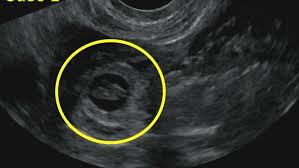

Στη συνέχεια, εξειδικεύτηκα στην εμβρυομητρική ιατρική & τον προγεννητικό έλεγχο, από τον παγκοσμίου φήμης καθηγητή Κύπρο Νικολαΐδη, επί 3 έτη, ολοκληρώνοντας τον κύκλο σπουδών που απαιτείται και απέκτησα μεγάλη εμπειρία στους εμβρυϊκούς υπερήχους και τις επεμβατικές εξετάσεις.

Έλαβα όλες τις πιστοποιήσεις για την εκτέλεση όλων των υπερηχογραφήματων και των ενδομητρίων επεμβάσεων στην εγκυμοσύνη.

Όλοι οι έλεγχοι γίνονται με βάση τις οδηγίες του Fetal Medicine Foundation.